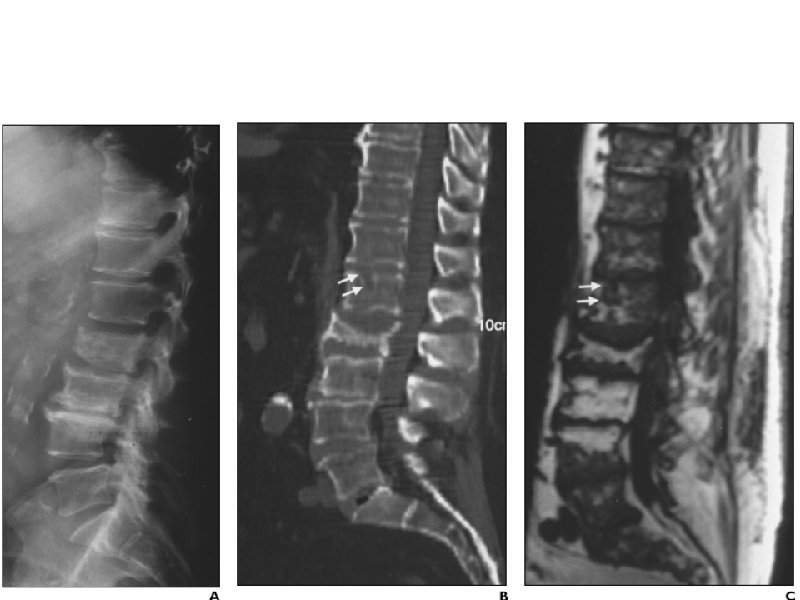

Лимфомы

Неходжкинские лимфомы низкой степени злокачественности